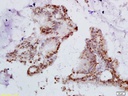

人类乳头状瘤病毒16/18 E6抗体

目录号:bs-1719R

商品规格:200ul